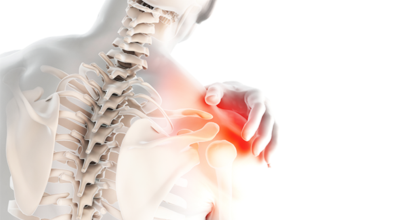

오늘 포스팅 주제는 현장 근로자들이나 운동선수 혹은 과격한 활동을 하시는 분들이 많은 고통을 호소하시는 회전근개파열 증상과 예방법 대해 알아보도록 해요.

회전근개 증후군은 회전근개에 변형과 파열이 생긴 질환을 말합니다. 회전근개란 어깨와 팔을 연결하는 4개의 근육(극상근, 극하근, 소원근, 겹갑하근) 또는 힘줄로 이루어져 있는 것으로 보입니다. 어깨 근육통을 막연히 오십견으로 알고 방치하다가 치료 시기가 늦어지는 경우가 있답니다. 적절한 시기에 병원에 가는 것이 필요합니다.

회전근개가 파열되는 경우 어깨에 통증이 생겨나게 되어요. 회전근개는 어깨 회전 운동에 영향을 줌으로 인해 팔을 들어올리는 동작에 제약이 생기기도 합니다. 이러한 증상은 오십견 증상과 비슷하기도 한데요. 수동적 움직임도 제한되는 오십견과는 달리 다른 사람의 도움을 받게 되면 팔을 들어올릴 수 있다는 차이가 있답니다.

회전근개파열은 가만히 서 있는 경우 통증이 줄어들기도 하지만 눕는 경우 통증이 더 심해지며 통증이 발생한 부분으로 돌아 눕기가 어려워 수면 장애를 동반할 수도 있죠. 그리고 어깨는 수시로 쓰이는 부위인 만큼 통증이 발생하다 보면 일상에도 큰 불편함을 줄 수 잇어 초기에 치료를 받는 것이 좋습니다.